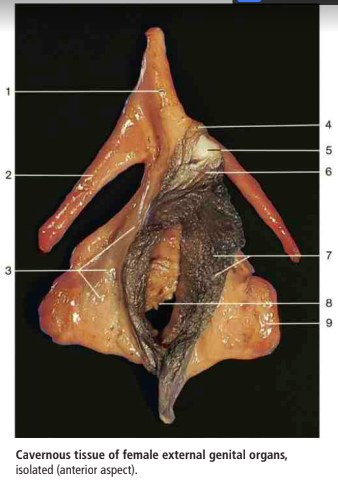

Label A-E

A

A: vagina

B: crus of clitoris

C: labia minoria

D: glands of clitoris

E: cervix